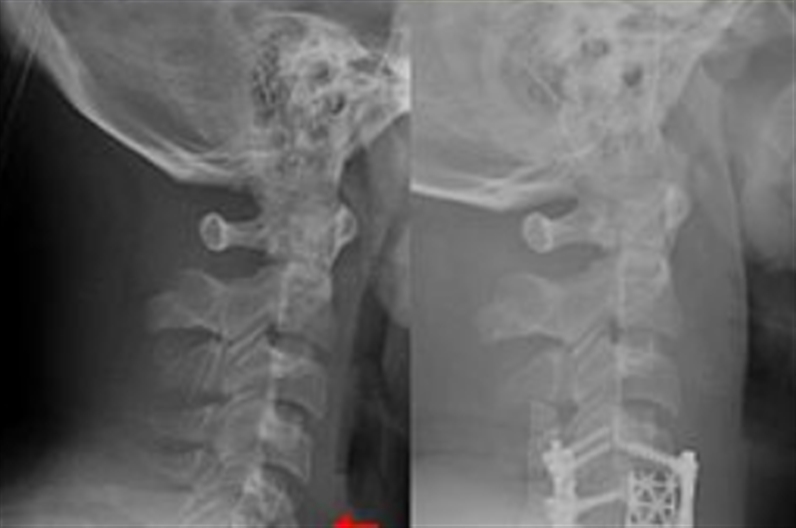

Orthopedics

Dr. Behzad Taleban